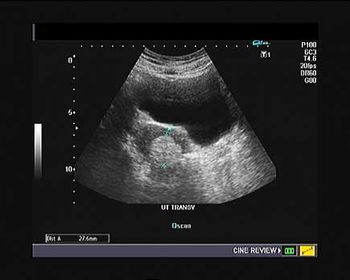

Challenge your diagnostic skills with these images from a young woman with right pelvic pain and a history of amenorrhea.